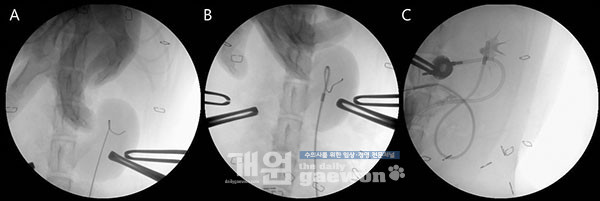

C-arm(GE healthcare, OEC® 9800 Plus)을 이용하여 guide-wire가 renal pelvis에서 curl의 형태인지 확인합니다(A).

Guide-wire 위로 catheter를 진입시킬 때 radiopaque maker를 확인하여 multi-fenestrated loop의 끝 부분이 renal pelvis에 있는 것을 확인했습니다(B).

Pyelogram을 실시하여 조영제가 새지 않는 것과 카테터의 위치가 정확한 지에 대한 평가를 실시했습니다(C)(그림 4).